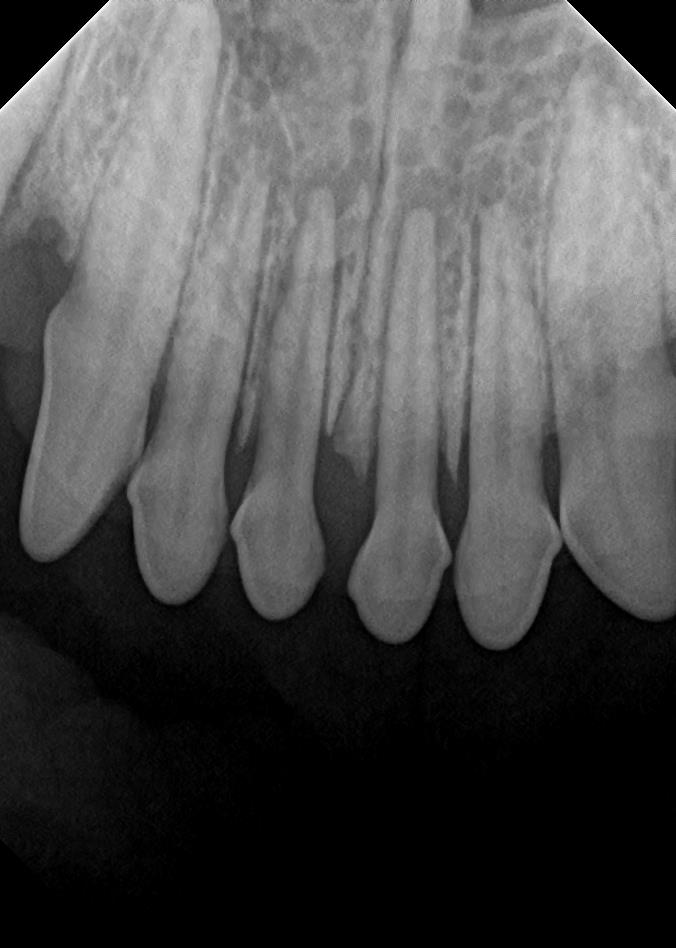

Examples of dental problems:

At A Couple of Vets, our animal hospital staff is well-versed in the latest dental cleaning techniques to remove plaque and tarter from the teeth’s surface as well as from below the gum line. We perform dental x-rays at every cleaning to ensure that the teeth are completely healthy. They may look good on the surface, but many problems occur below the gum line and are only visible with x-rays.